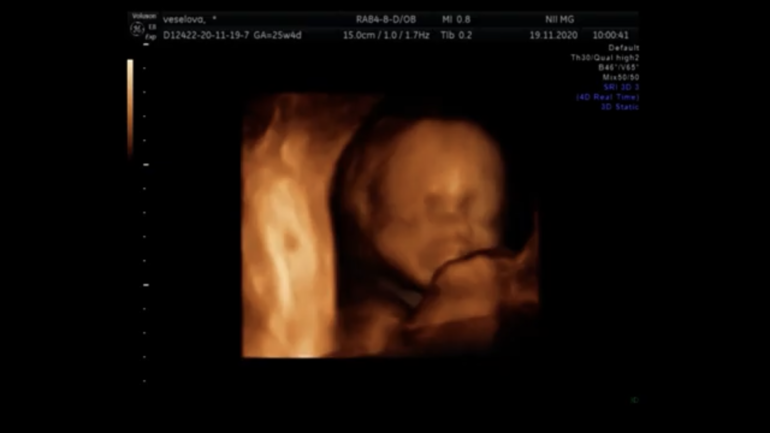

Ну и наше фото.

Очень похож на моего старшего сына:)

Курносый парень😌